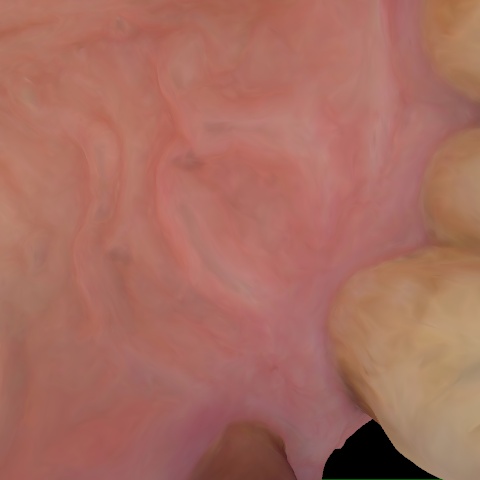

Annotated as "Good"